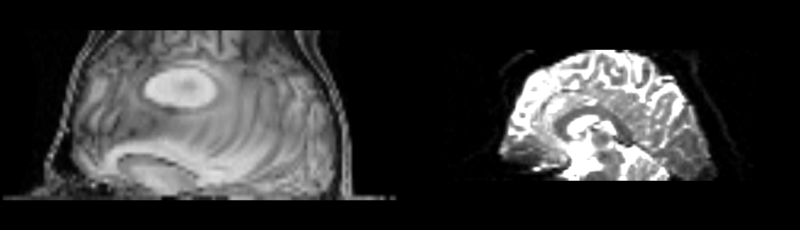

Original file(1,480 × 425 pixels, file size: 190 KB, MIME type: image/png)

Registration of t1 weighted image to DTI space via a bspline only registration.

current14:52, 4 May 2009Thumbnail for version as of 14:52, 4 May 20091,480 × 425 (190 KB)Rauscha (talk | contribs)Registration of t1 weighted image to DTI space via a bspline only registration.